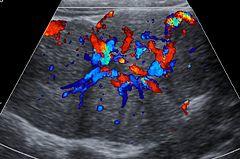

Ultrasound of malformed vessels within the fibrous scar of FNH.

Focal nodular hyperplasia's most recognizable gross feature is a central stellate scar seen in 60–70% of cases. Microscopically, a lobular proliferation of bland-appearing hepatocytes with a bile ductular proliferation and malformed vessels within the fibrous scar is the most common pattern. Other patterns include telangiectatic, hyperplastic-adenomatous, and lesions with focal large-cell dysplasia.[2] Rarely, these lesions may be multiple or can occur as part of a syndrome with hemangiomas, epithelioid hemangioendothelioma, hepatic adenomas, fibrolamellar hepatocellular carcinoma, vascular malformations of the brain, meningiomas, and/or astrocytomas.[2]